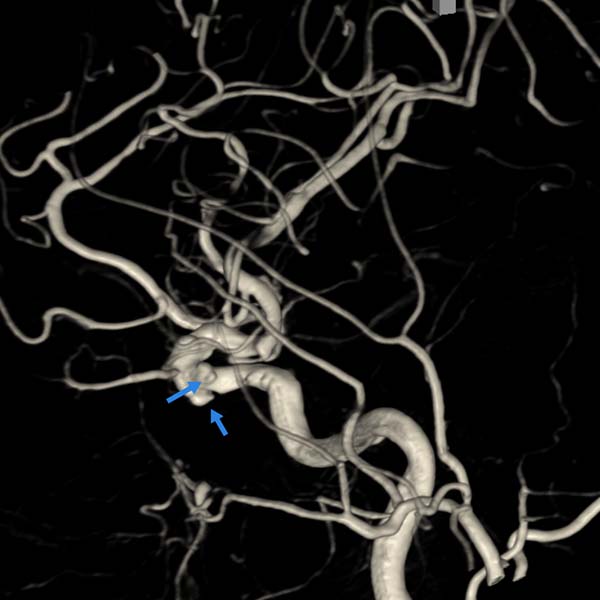

▲左颈内动脉3D-DSA显示两个动脉瘤(蓝箭头)